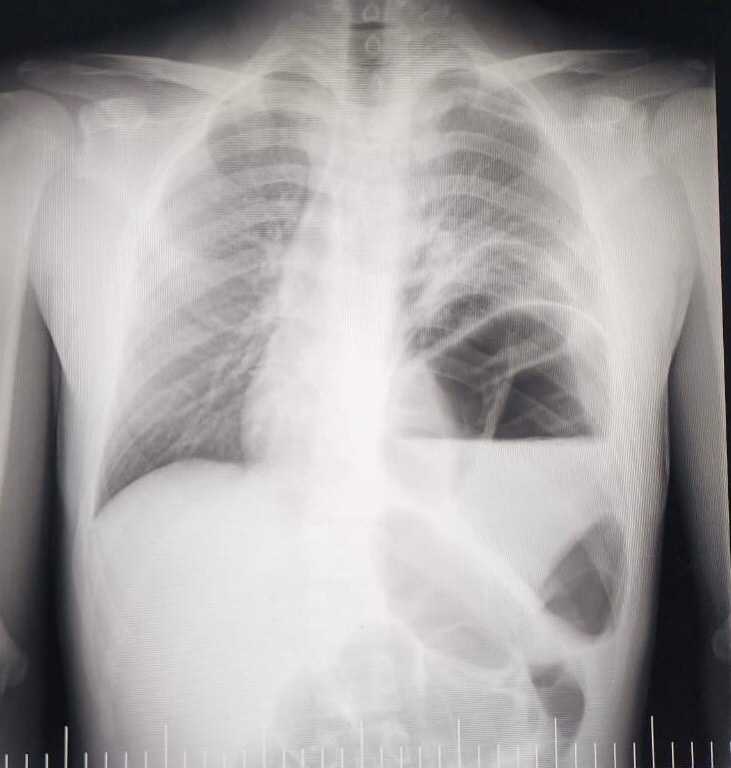

Воронежские врачи 11 отделения БУЗ ВО «ОДКБ №2» прооперировали за сутки сразу двоих детей. Пациенты, с довольно редким пороком развития - ложная диафрагмальная грыжа,в экстренном порядке поступили в больницу в конце января. Во время операции врачи установили, что в грудную клетку переместились: желудок, селезенка, поперечная ободочная кишка, сальник и участок тонкого кишечника. Операции прошли успешно. Дети несколько дней находились в отделении реанимации под круглосуточным наблюдением. Сейчас пациентов перевели в общую палату, где они проходят ранний курс реабилитации.

Специалисты объясняют, что такое диафрагмальная грыжа – это перемещение органов из брюшной полости (кишечник, желудок и т.д.) в грудную полость через естественное или патологическое отверстие в диафрагме (ложные), а так же путем выпячивания истонченного участка диафрагмы (истинные).

Фото:  БУЗ ВО «ОДКБ №2».